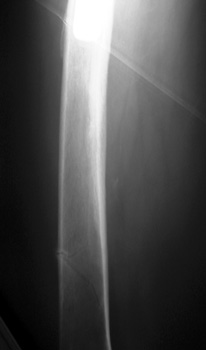

Most frequently occur near distal stem of femoral component

Osteopenia due to long periods of inactivity secondary to pain and disability predispose to insufficiency fractures after surgery when patients are ambulating more frequently.

Fracture distal to femoral stem

Stress riser distal to prosthetic